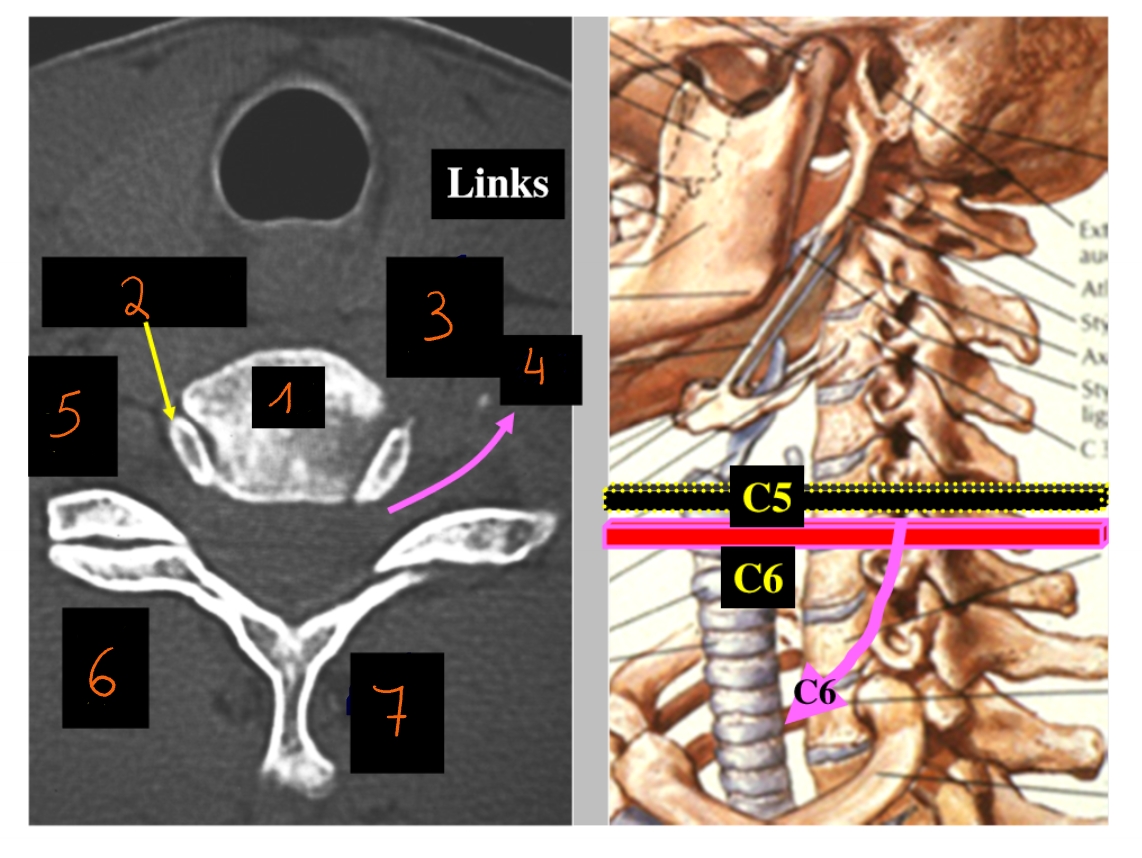

CT-scan

maakt dwarse doorsneden van de mens → salami

corpus C5

processus uncinatus C6

foramen intervertebrale

spinale zenuw C6

processus articularis superior C6

processus articularis inferior C5

processus spinosus C5